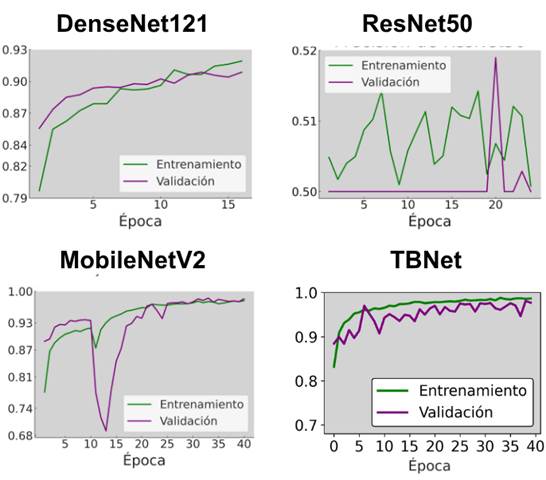

Por otro lado, la Figura 9 presenta las curvas de precisión de entrenamiento y validación para los modelos DenseNet121, ResNet50, MobileNetV2 y TBNet, permitiendo comparar su comportamiento durante el proceso de aprendizaje. DenseNet121 muestra un incremento progresivo y estable de la precisión, con curvas cercanas y sin fluctuaciones bruscas, lo que indica una convergencia consistente. En contraste, ResNet50 exhibe una precisión más baja y considerablemente irregular, con oscilaciones marcadas tanto en entrenamiento como en validación, lo que evidencia dificultades para estabilizar el aprendizaje. MobileNetV2 alcanza valores altos de precisión, pero presenta una caída repentina en validación en las primeras épocas, seguida de una recuperación posterior, lo que refleja cierta inestabilidad inicial antes de converger. Por su parte, TBNet muestra una precisión que aumenta rápidamente y mantiene valores elevados a lo largo del entrenamiento, aunque con variaciones moderadas en la curva de validación que indican un proceso de ajuste más dinámico.

Figura 9. Curva de precisión por época de los modelos evaluados.

Elaboración: Los autores.

En conjunto, los resultados obtenidos permiten establecer una comparación sólida entre las cuatro arquitecturas evaluadas. DenseNet121 demostró ser el modelo con el entrenamiento más estable, presentando curvas de pérdida y precisión limpias, sin fluctuaciones bruscas y con una clara ausencia de señales de sobreajuste o subajuste. Sin embargo, al analizar el desempeño cuantitativo reflejado en las métricas finales se observa que TBNet supera consistentemente al resto de arquitecturas en las medidas más críticas para la detección de tuberculosis. En dichas medidas, TBNet alcanzó la mayor accuracy, precisión y un F1-score, situándose por encima del rendimiento logrado por MobileNetV2 y DenseNet121. Por ende, se determina que TBNet fue el modelo que presentó el mejor equilibrio entre aciertos y errores, destacándose especialmente por su precisión y su bajo número de falsos negativos, una característica esencial en aplicaciones clínicas donde la omisión de un caso positivo podría tener consecuencias críticas.

Si bien DenseNet121 mostró una mayor estabilidad durante el entrenamiento, reflejada en curvas de pérdida y precisión más uniformes, los resultados cuantitativos demuestran que la estabilidad visual del aprendizaje no siempre se traduce en un mejor rendimiento clínico. En este sentido, TBNet logró maximizar métricas críticas como accuracy, precisión y F1-Score, además de minimizar los falsos negativos, indicador clave en escenarios diagnósticos. Esta observación es consistente con estudios recientes que advierten que, en aplicaciones médicas, la priorización de métricas clínicas debe prevalecer sobre indicadores computacionales, ya que el impacto de un falso negativo puede comprometer el tratamiento oportuno del paciente (Rahman et al., 2020; Sánchez Figueroa et al., 2024).

Aunque DenseNet121 presentó la curva de pérdida más estable y un proceso de aprendizaje visualmente más consistente, los resultados cuantitativos mostraron que la estabilidad gráfica no siempre se traduce en el mejor desempeño final. En este estudio, TBNet demostró ser el modelo más eficiente para la detección de tuberculosis, aun cuando su curva de pérdida exhibió oscilaciones notables durante las primeras épocas. Estas variaciones no afectaron su capacidad discriminativa y el modelo logró converger adecuadamente y produjo las métricas más altas en precisión, accuracy y F1-Score.